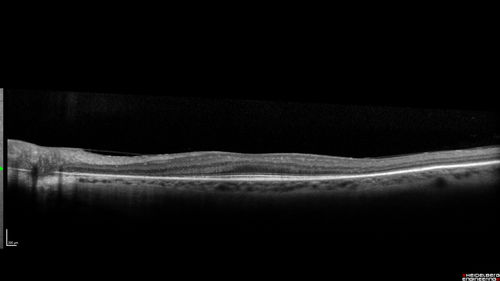

Retinitis Pigmentosa with Cystoid Macular Edema responsive to topical carbonic anhydrase inhibitors

67 year old female  She thought it was time to have her glasses changed.She has no family history of reitnal disease and has never been diagnosed with a problem.   She started having night vision trouble the last year.  Two sisters and a brother with normal vision.